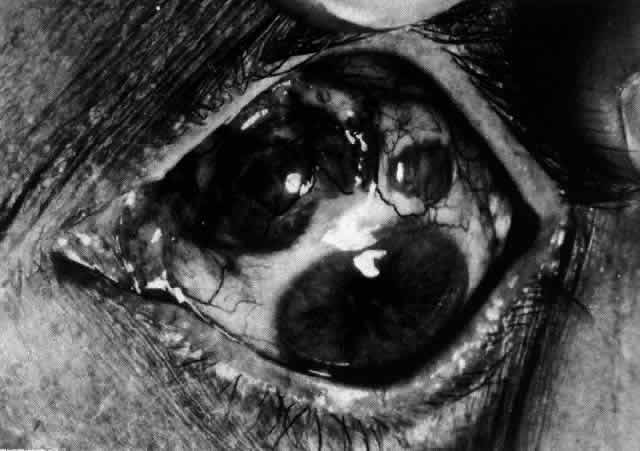

Necrotizing anterior scleritis without adjacent inflammation appears to be a well-defined condition with little relation in clinical features to necrotizing scleral disease, even though the pathology is similar and the final result is the same. Scleromalacia perforans is characterized by the almost total lack of any symptoms. It occurs almost exclusively in patients with long-standing polyarticular rheumatoid arthritis, the majority of whom are female (Figs. 49 and 50; Color Plate 1E).

Fig. 49. A white necrotic plaque developing in an area of sclera with practically no surrounding inflammation in a 60-year-old woman who had had Crohn's disease for 17 years.

Fig. 50. Scleromalacia perforans after treatment. The very thin sclera is covered by conjunctiva only and a few remaining large blood vessels. (Courtesy of Mr. HE Hobbs)

The anterior sclera loses its covering of episclera and develops an area of yellow-white necrotic slough over many months; this eventually separates or is absorbed, leaving the underlying choroid covered by either conjunctiva or nothing at all. As with necrotizing disease, the choroid does not bulge into this ectatic area; but unlike necrotizing disease, spontaneous healing of even small perforations is very limited once the necrotic tissue has been removed (see Fig. 50).

Fluorescein angiography is not helpful, except to indicate areas of vascular closure in an otherwise extremely thin, atrophic episcleral tissue.4 The formation of a sequestrum appears to be caused by arteriolar closure as opposed to the venular disease seen in the other forms of necrotizing scleritis.